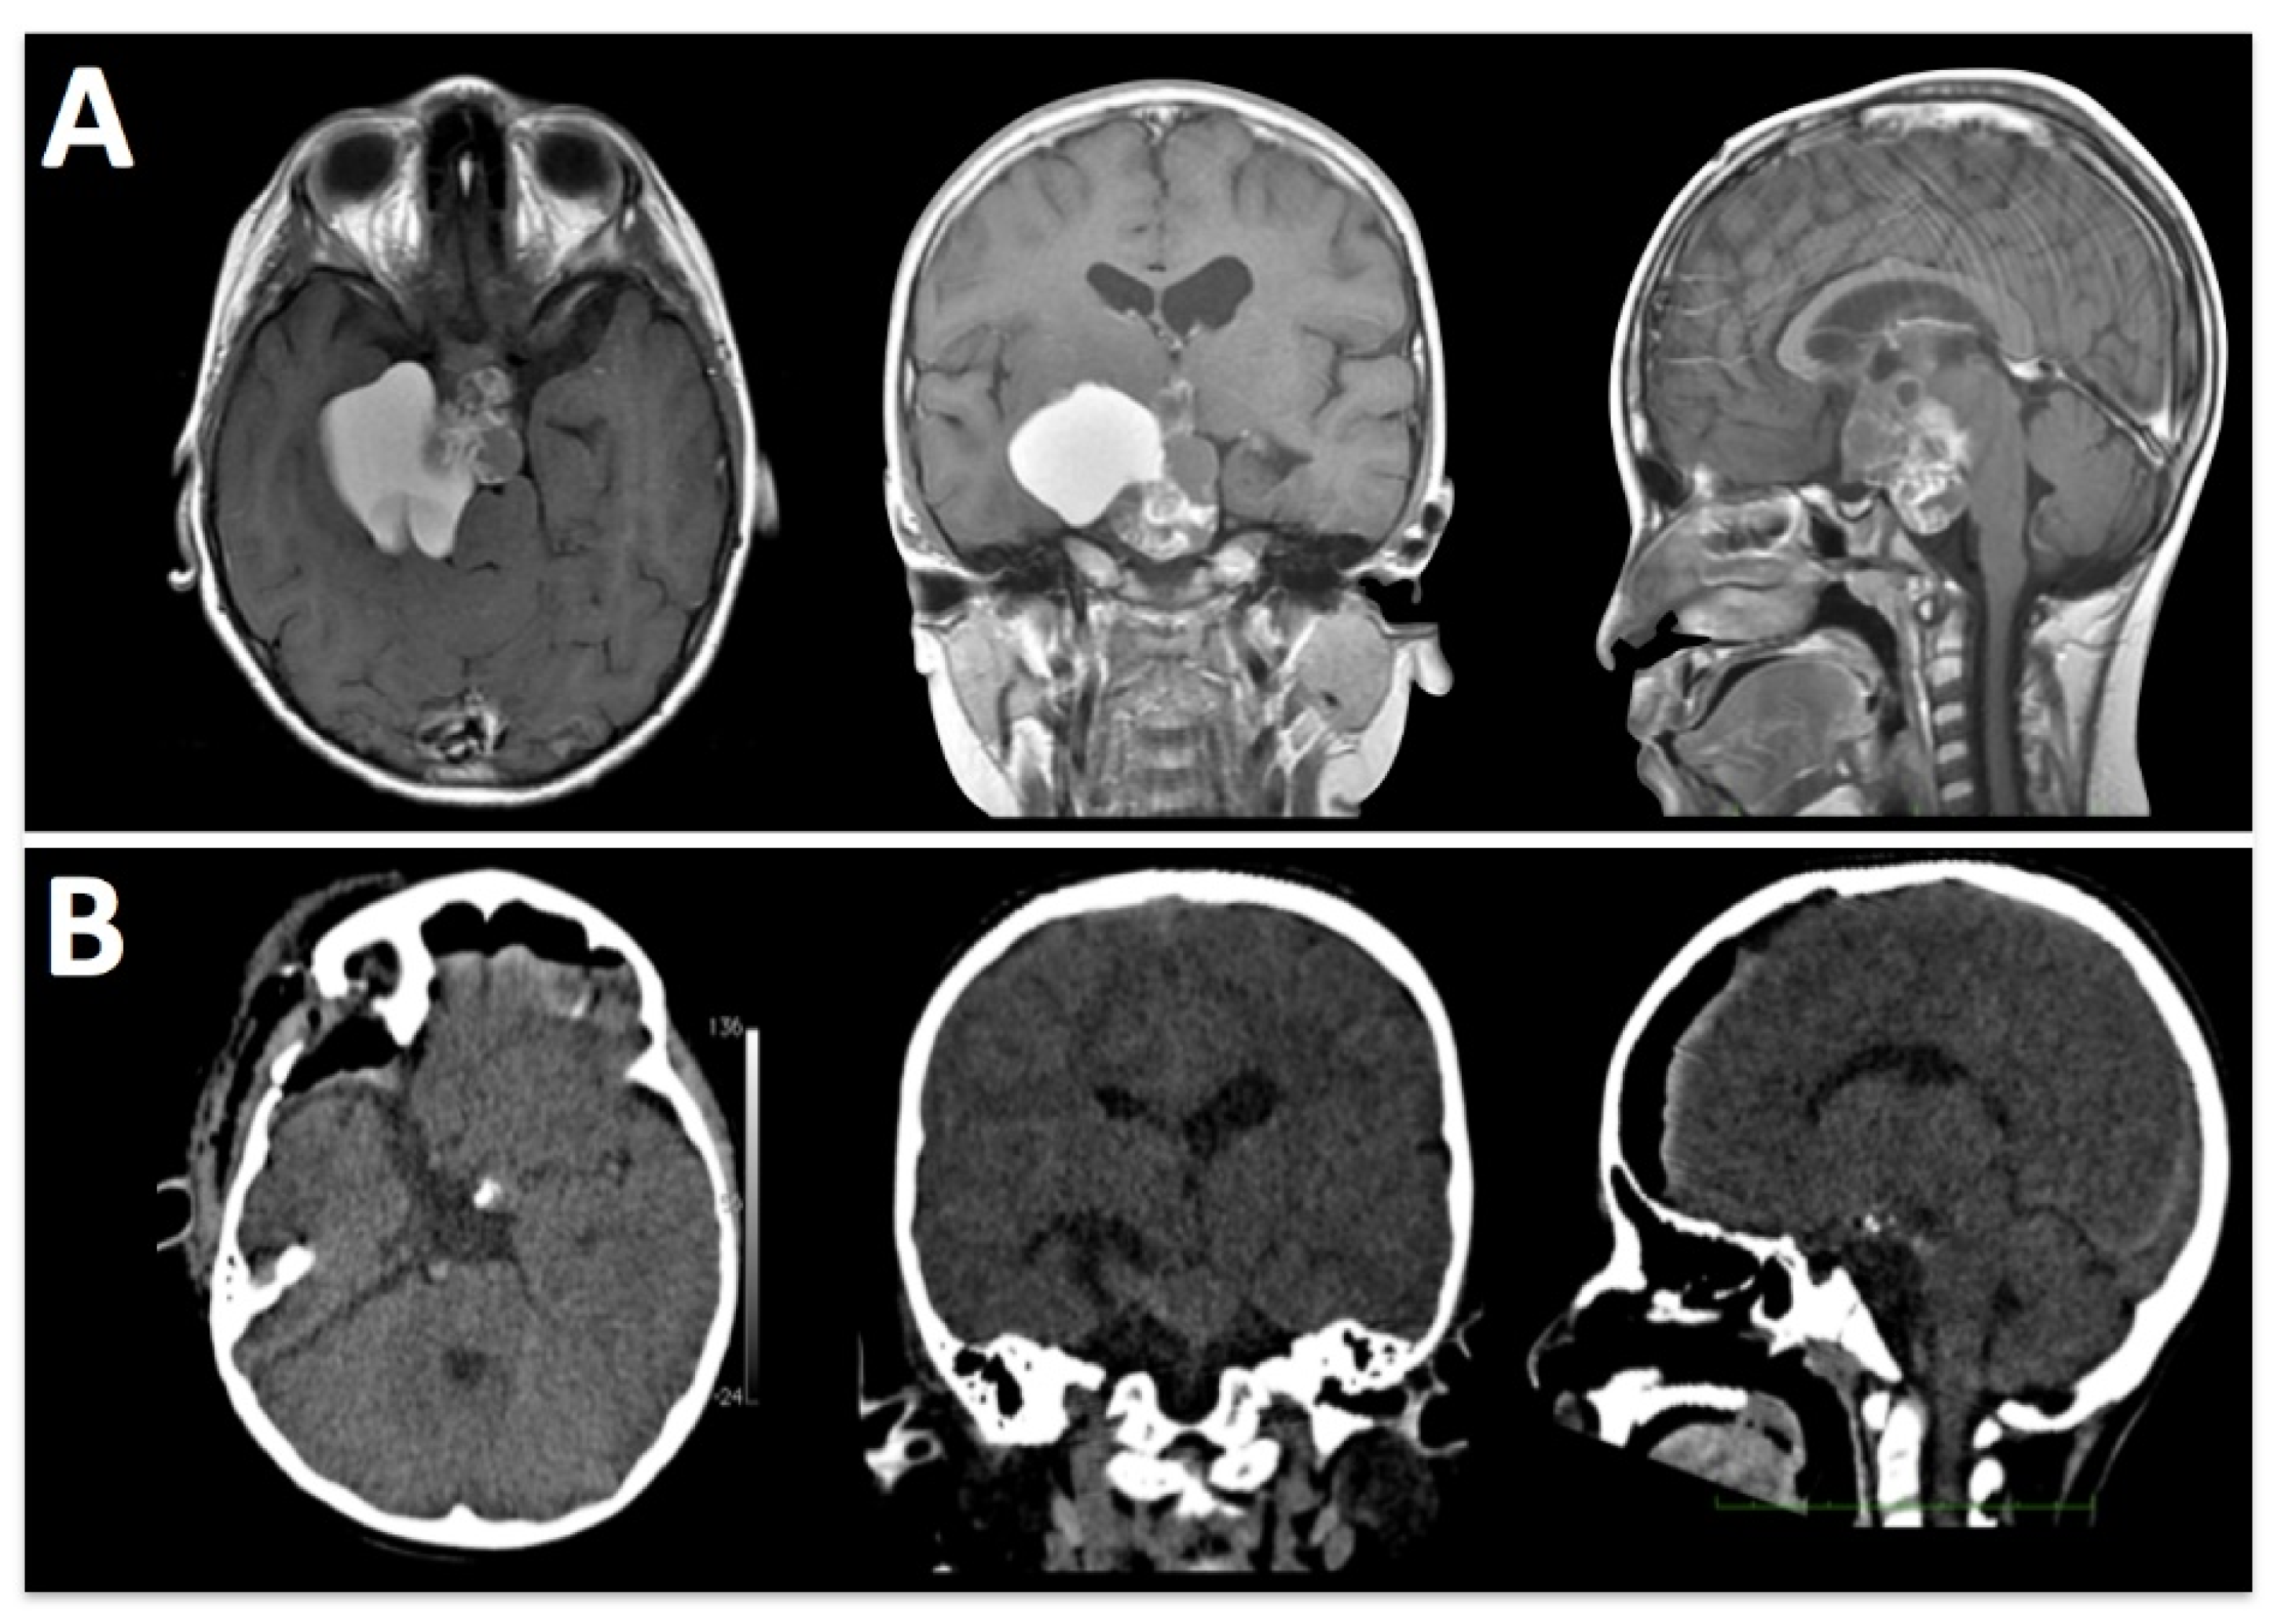

Figure 4. A 12-year-old girl admitted with diabetes insipidus and a growth delay. (A) Pre-operative MRI shows a sellar mass with extension to the infundibular stalk. (B) Postoperative MRI shows a gross-total resection.

In this study, the extended sphenoid ridge approach (E-SRA) provided comparable exposure with other skull base approaches, while minimizing the need for extensive soft tissue dissection (Figure 4).